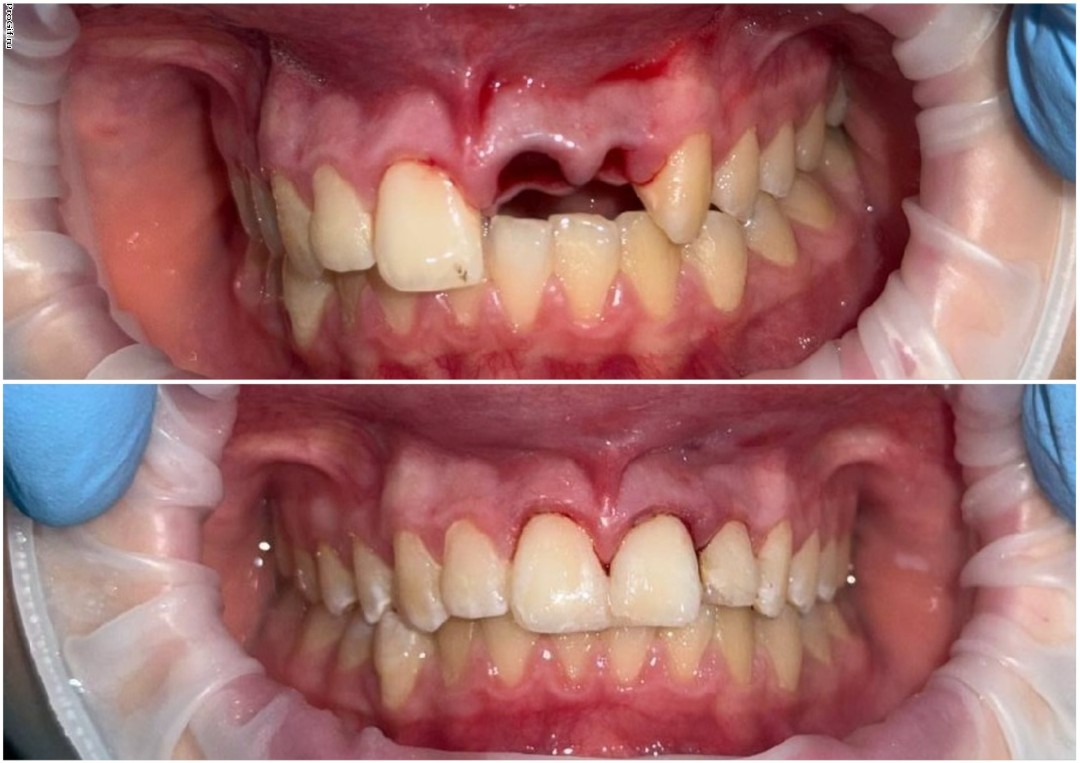

Атравматичное удаление зубов – наиболее безболезненная и щадящая процедура, которая практически не травмирует десну и костную ткань.

Зуб извлекается частями, что позволяет не травмировать окружающие ткани.